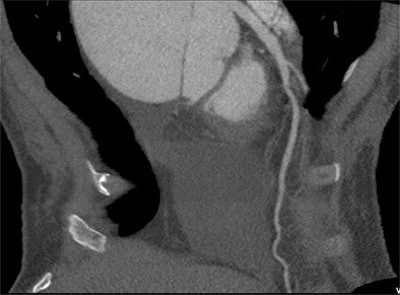

Images of the whole aorta were acquired using a wide-volume protocol; each volume was scanned in a single heartbeat with 16-cm anatomic coverage. The second volume was positioned to cover the whole heart to ensure that all the segments of coronary arteries were in the same dataset. The table is stationary during each acquisition, and then moves to the next location for the next CT data acquisition. Patient is a 23-year-old woman with Marfan syndrome combined with coronary-pulmonary fistula, and a Stanford type A aortic dissection. All images courtesy of Dr. Yu Li.

For all the power of modern CT scanners to generate exquisitely detailed images of the vasculature, scanning the aorta without gating is risky because artifacts in the ascending aorta can simulate the appearance of a dissection flap, leading to an incorrect diagnosis of dissection. In their study, Li and colleagues aimed to investigate the feasibility of using a prospective ECG-gated wide-volume protocol in CTA of the whole aorta and coronary arteries (CA).

CTA of the aorta is a common imaging technique due to its speed and resolution, according to the researchers. But motion in the ascending aorta can be a problem without ECG gating. Using 320-detector-row CT, image quality is acceptable throughout, and for Stanford type A aortic dissection, CTA showed the relationship between the intimal flap, and the aortic valve and the coronary ostium "without obvious motion artifacts," they stated.